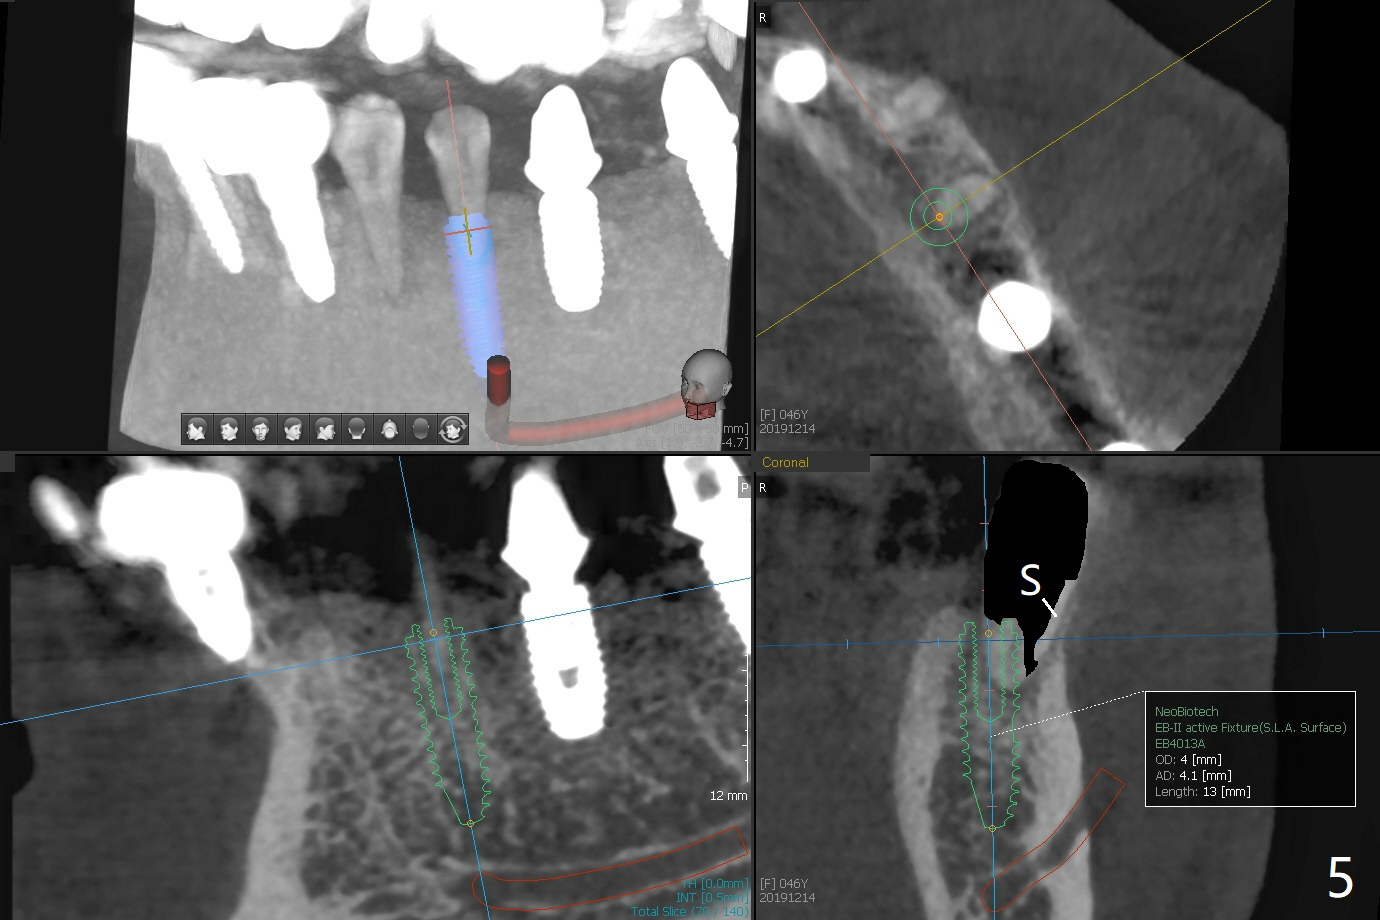

Re-analysis of preop CT reveals extensive bone loss around #18 (Fig.1 (lingual view)). Blood is withdrawn for sticky bone. After implant placement (Fig.2), sticky bone is placed at #18 (Fig.3 red dashed line (yellow: superior border of the Inferior Alveolar Canal)). PRF membrane and an immediate provisional FPD (#18-20) further keep the bone graft in place for healing. Four months postop, the patient reports difficulty in mastication on the left and requests extraction of the tooth #20 for implant (Fig.4). The implant will be placed lingually, while socket shield will be performed buccally (Fig.5 S) to keep bone graft in place. The implant at #19 is equicrestal (Fig.6); the one at #18 is apparently supracrestal buccally (Fig.7). Since there is a lot of scattering from nearby crowns, the implant at #20 will be placed free hand. To overcome the thick dense lingual plate (Fig.8 L), osteotomy is initiated (Fig.9 red line) in the middle of the lingual wall of the extraction socket (black area) on the top of the socket shield (S). After the last drill (3.5x11.5 mm, Fig.10 pink) and before 4x11.5 mm implant, use Lindamann bur to remove the coronal portion of the lingual plate (Fig.11 red line) to prevent implant buccal deviation.